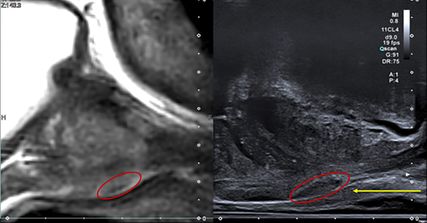

Abb. 1: MRT (links) und Ultraschall (rechts) der Prostata im sagittalen Anschnitt mit suspektem Areal (roter Kreis) in der apikalen Peripherenzone. Der gelbe Pfeil stellt den perinealen Punktionsweg der Biopsienadel dar

Wie bereits erwähnt, ist aber vor allem die diagnostische Genauigkeit der Prostatabiopsie das relevanteste Qualitätskriterium. Diesbezüglich erlaubt eine transperineale Prostatabiopsie eine genauere Beurteilung der peripheren Zone, da aufgrund des Punktionsweges die Biopsiezylinder innerhalb der Peripheren vom Apex bis zur Basis entnommen werden.7 Die transrektale Methode erfasst zwangsläufig sowohl die periphere als auch die Transitionalzone. Darüber hinaus bietet der longitudinale Schallkopf einer perinealen Biposiesonde die Möglichkeit, die Prostata hochauflösend in sagittaler Schnittführung in Gänze von Apex bis Basis darzustellen. Dies ermöglicht bei vielen Patienten eine gute Darstellung von Prostatakarzinomen im B-Bild und verbessert die Genauigkeit der Biopsie (Abb. 1).